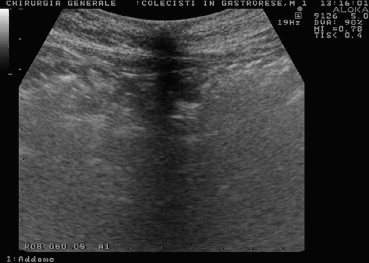

Fig. 1.

US shows adherence of peritoneum to the sub-umbilical fascial layer.